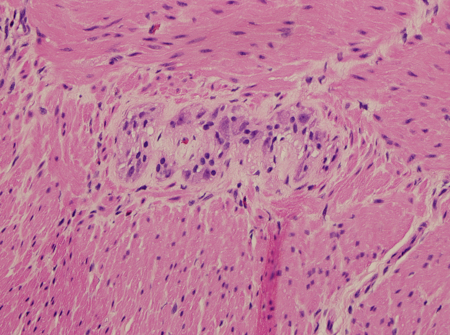

Rectal biopsy pathology will show an absence of ganglion cells in Hirschsprung's disease. It may also show the presence of hypertrophic nerves (greater than 40 micrometres in an infant less than 6 months), but this may be absent in patients with long-segment disease or total colonic aganglionosis (TCA).[53] Other immunohistochemical stains including calretinin, choline transporter, and acetylcholinesterase may be useful ancillary markers.[53][54]

[Figure caption and citation for the preceding image starts]: Hematoxylin and eosin showing ganglion cells in the myenteric plexusFrom the personal collection of Lily Cheng, MD; used with permission [Citation ends].